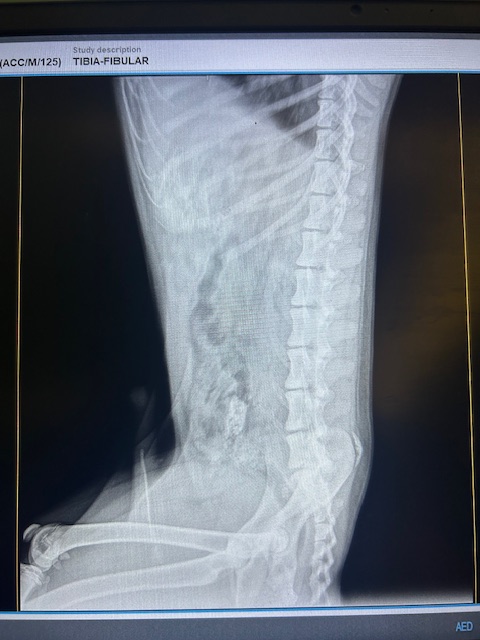

Ben wurde uns gemeldet, weil er nur auf drei Beinen lief – wir haben nicht gezögert und uns sofort auf den Weg gemacht. Vor Ort konnten wir ihn schnell sichern und direkt zum Röntgen bringen. Die Diagnose: Ein komplizierter Bruch. Nach ein paar Tagen Ruhe bei uns im Center folgte die Operation. Leider verlief diese nicht wie sie sollte. Trotz aller Bemühungen unsererseits und einer intensiven Genesungszeit nutzt Ben das operierte Bein nur selten und nicht wie ein gesunder Hund es tun würde. Weitere Eingriffe hier vor Ort würden seine Lebensqualität nicht verbessern, da die medizinischen Möglichkeiten hier leider Grenzen haben.